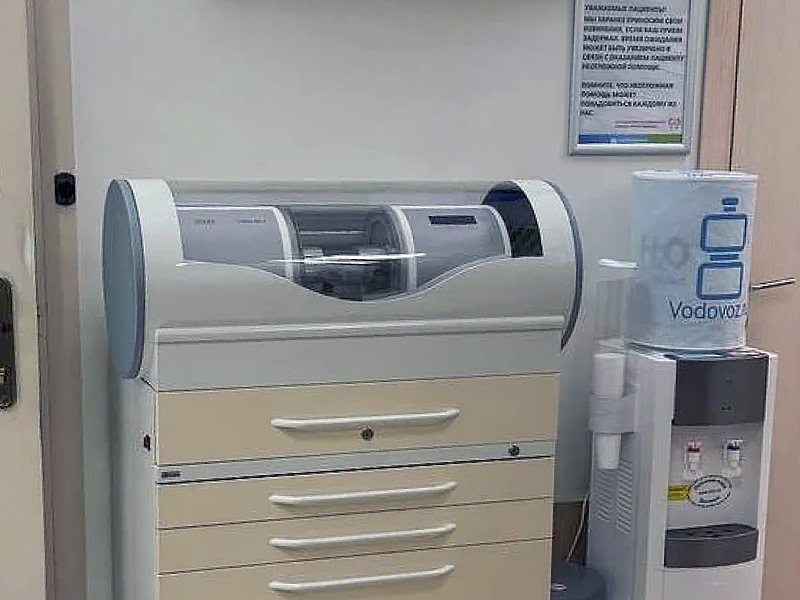

Наше оборудование